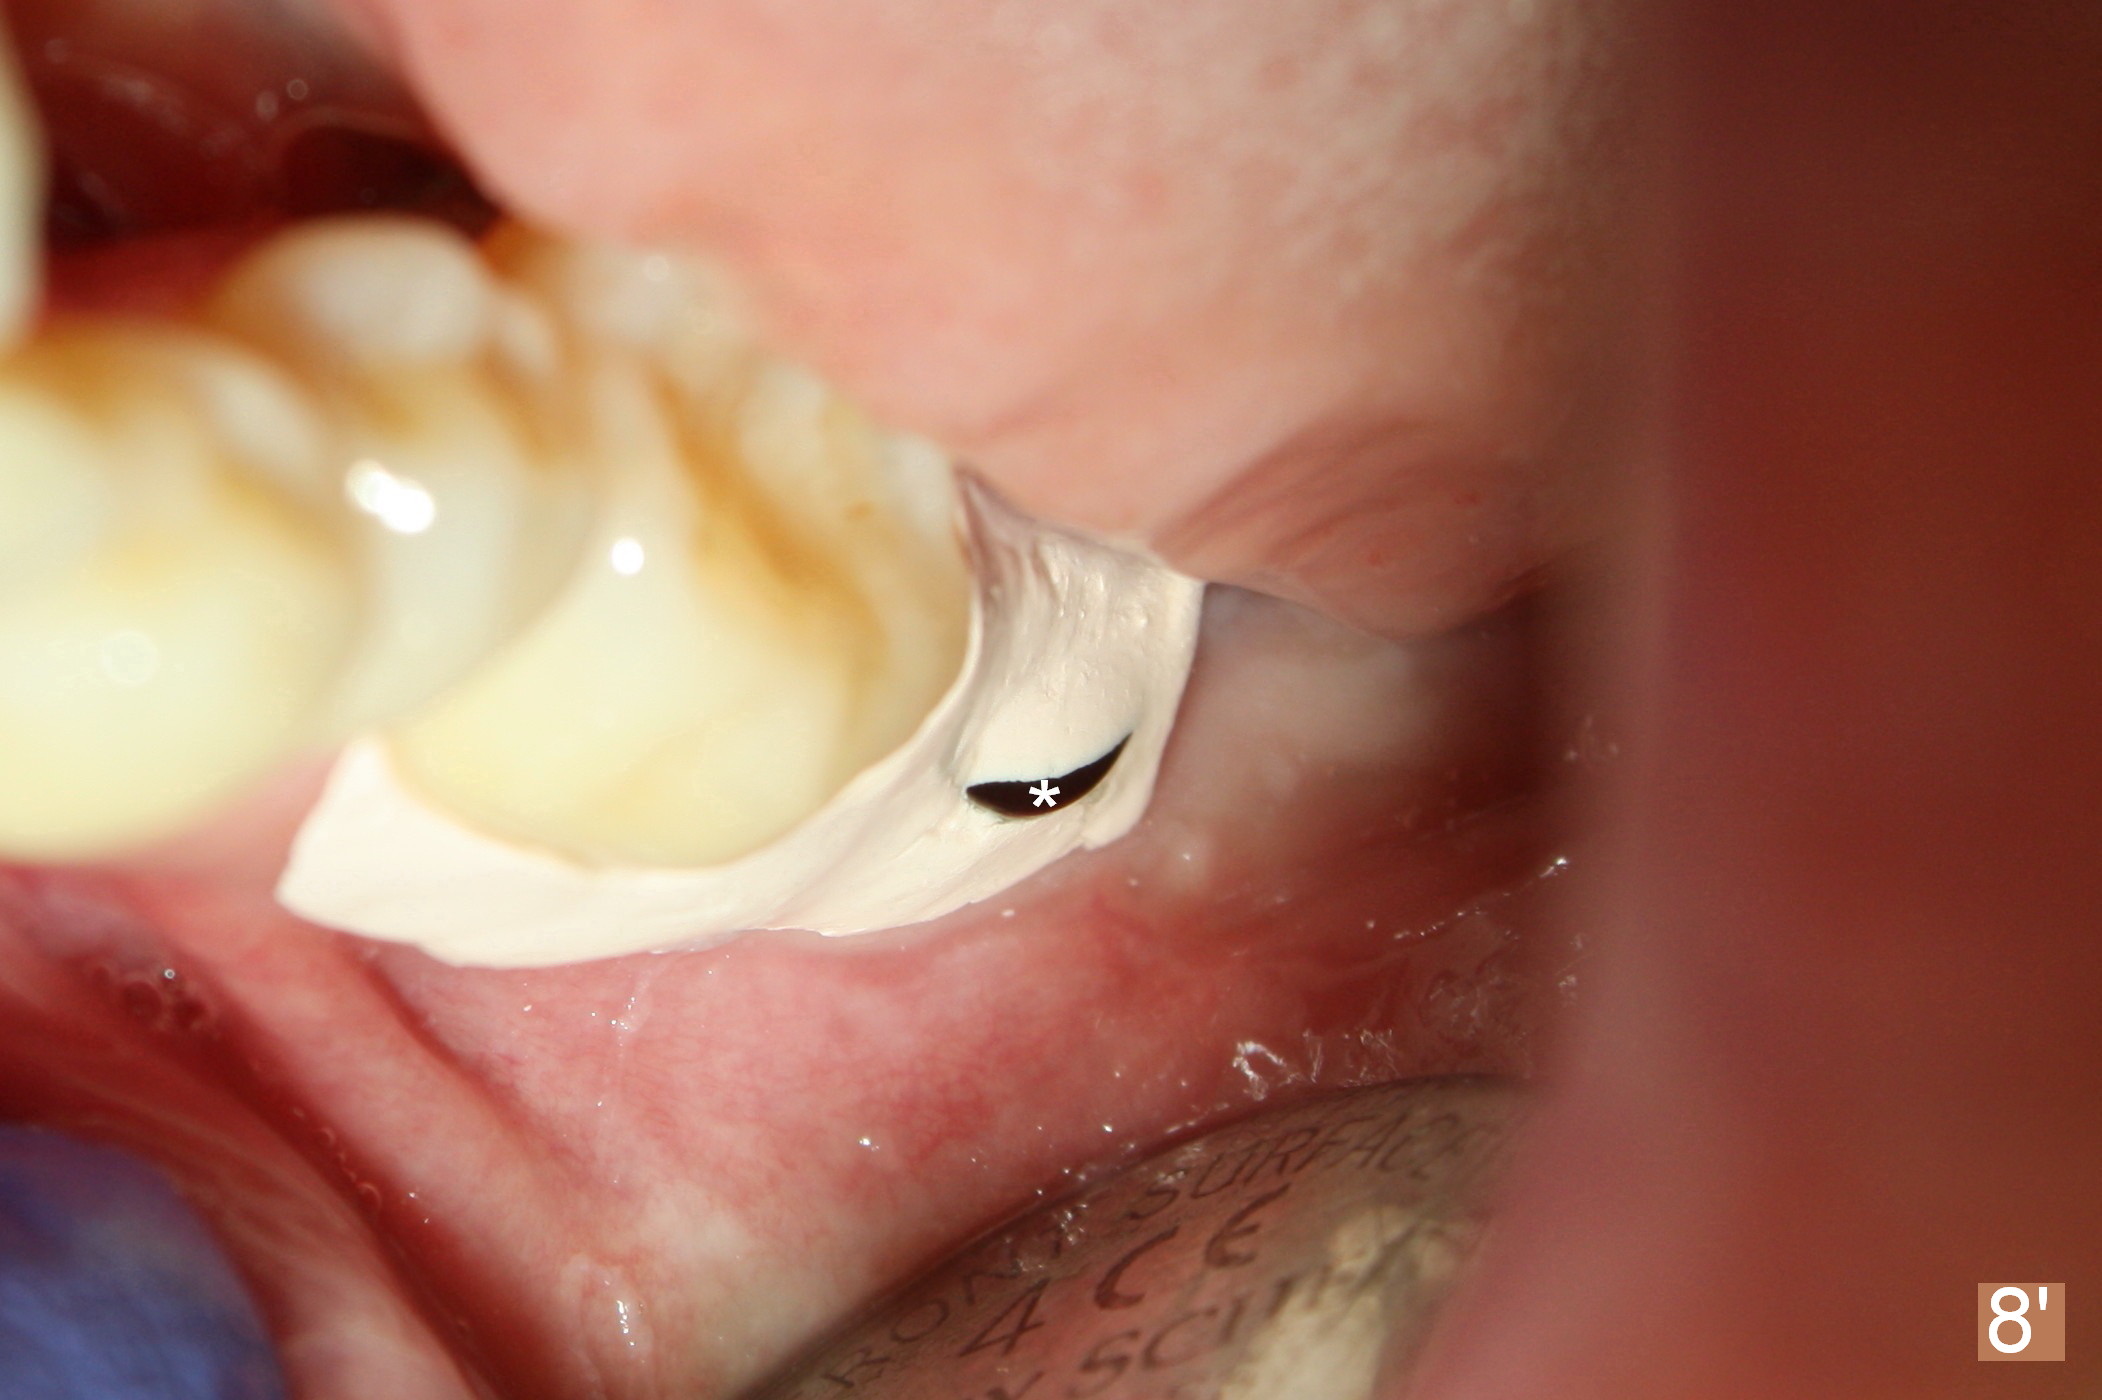

A 48-year-old lady is a dental phobic, requesting extraction of the lower left 2nd molar (Fig.1). She returns for implant placement 9 months post extraction (Fig.2). The ridge is mildly to moderately atrophic. It appears that a 5x12 mm implant is appropriate for the site (Fig.3). For safety, osteotomy is initiated at the depth of 10 mm; it appears that there is enough height for a 12 mm implant (Fig.4). The depth is controlled by drill stopper (Fig.5 S). Finally a 5x12 mm implant is apparently safely placed (Fig.6). A healing abutment is placed and the incision is sutured with 4-0 Chromic gut (Fig.7). Perio dressing is applied around the healing abutment for wound protection (Fig.8). It appears that the healing abutment (Fig.8': *) helps stabilize the perio dressing, which remains in place 1 week postop. When the perio dressing is removed, the wound around the healing abutment is healing (Fig.9). There is no bone loss around the implant 3 months postop (Fig.10 (H: healing abutment), or 16 months postop (i.e., 9 months post cementation, Fig.11,12). The patient complains of pain when she chews with the implant crown, but pain stops whenever she does not bite. Percussion does not elicit any discomfort. The gingiva is healthy. There is possibility of the buccal plate being thin or the lingual plate being perforated in the submandibular fossa. If the discomfort remains the same next 6 months, CBCT will be prescribed.